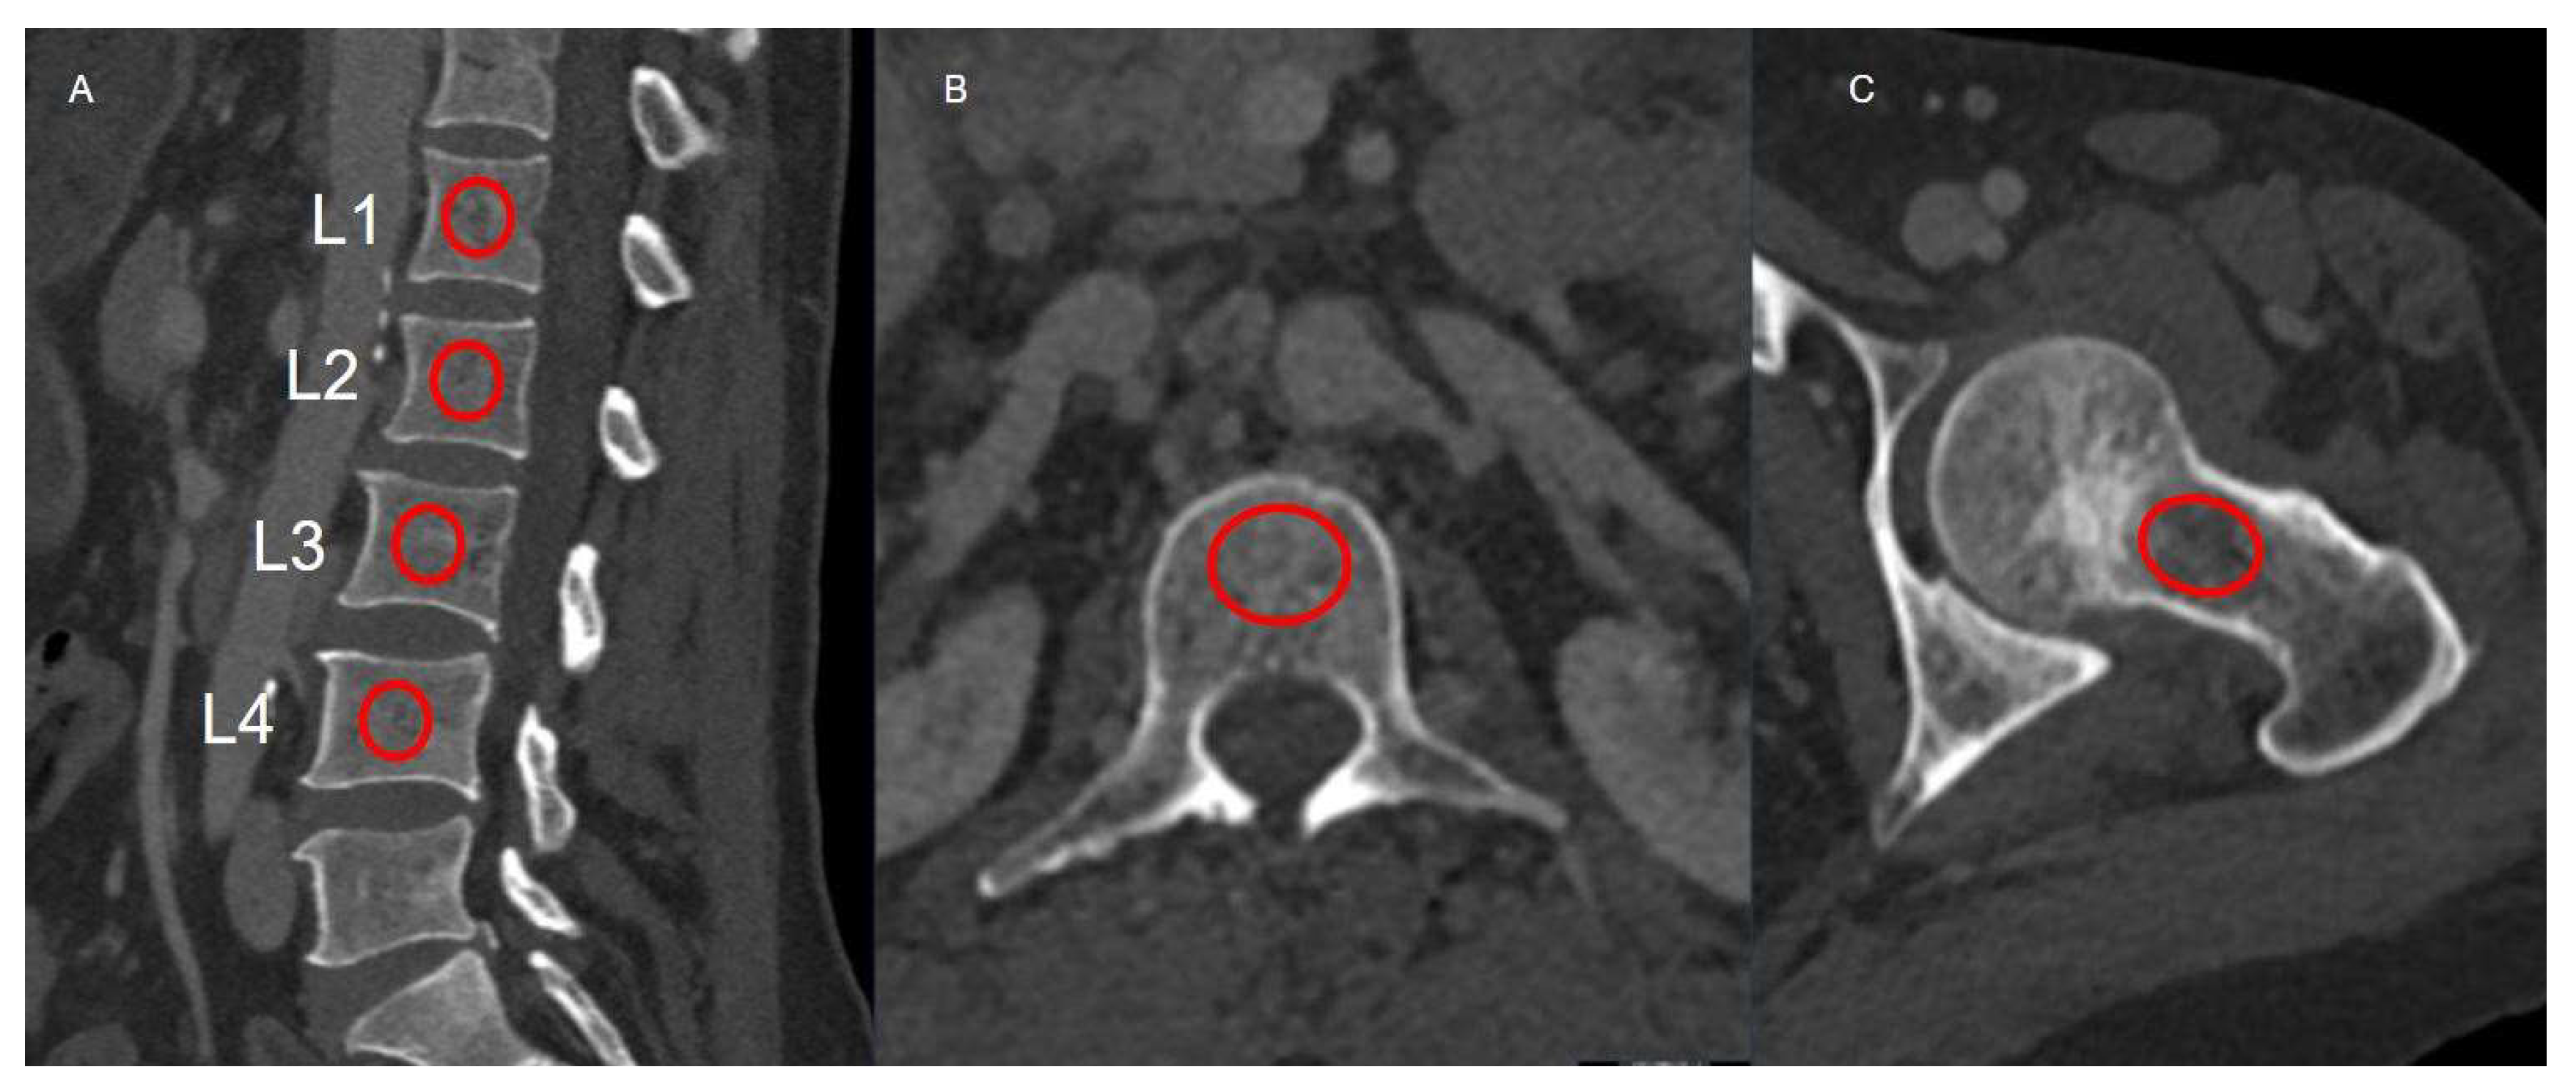

All CT examinations were performed as part of routine post-transplant surveillance using multi-detector scanners, including the Somatom Definition 256-slice system (Siemens Healthineers, Erlangen, Germany) and the Aquilion 64-slice system (Canon Medical Systems, Otawara, Japan; formerly Toshiba Medical Systems), during the venous phase after intravenous contrast administration. Imaging parameters were standardized across scanners: tube voltage of 120 kVp, automated tube current modulation, 1 mm slice thickness, and a 512 × 512 reconstruction matrix. Images were reconstructed using a standard soft-tissue convolution kernel in both axial and sagittal planes to provide optimal delineation of trabecular bone. Quantitative attenuation measurements were independently performed by two radiologists, each with more than ten years of experience in abdominal imaging, blinded to the DXA findings. Circular regions of interest (ROIs) were manually placed within the central trabecular portion of the L1–L4 vertebral bodies in both axial and sagittal reconstructions, carefully avoiding cortical bone, endplates, and adjacent vascular structures to ensure consistent trabecular sampling. For femoral measurements, the ROI was placed within the medial trabecular region of the femoral neck, just inferior to the physeal scar, with care taken to exclude cortical bone and the superior margin that is particularly susceptible to partial-volume effects. For each site, the mean HU value was recorded, and the average of L1–L4 measurements was used as the representative vertebral attenuation for subsequent analysis. Lumbar HU measurements were made in both sagittal and axial planes. Femoral HU measurements were performed only from the left side, consistent with DXA examination (Figure 1).

Figure 1.

Sagittal lumbar (A), axial lumbar (B), and femoral neck (C) CT images demonstrating regions of interest (red circles) used for HU measurements. The ROIs shown are for demonstration purposes only; actual quantitative measurements were performed using workstation-defined ovoid ROIs with a diameter of approximately 2–2.5 cm.